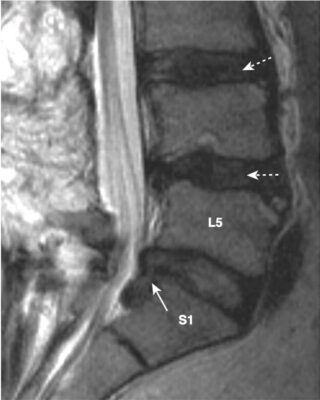

- Phần lớn thoát vị đĩa đệm xảy ra ở ba mức đĩa đệm thắt lưng dưới là L3-L4, L4-L5 (phổ biến nhất) và L5-S1. Hơn 60% trường hợp thoát vị đĩa đệm là sau bên. Vị trí thoát vị quyết định biểu hiện lâm sàng tùy thuộc vào rễ thần kinh nào bị chèn ép.

- Trên MRI, đĩa đệm thoát vị thường là phần lồi ra không đối xứng, khu trú của chất liệu đĩa đệm cường độ thấp, vượt ra ngoài giới hạn của vòng xơ (Hình 6).

- Sự giảm hàm lượng nước trong nhân nhầy dẫn đến cường độ tín hiệu của đĩa thấp hơn trên hình ảnh T2W (xem Hình 6).

- Ở cột sống thắt lưng, thoái hóa khớp diện nhỏ có thể gây hẹp và đặc xương các khớp diện nhỏ, thấy rõ nhất với hình chụp chếch. Thoái hoá khớp diện nhỏ dễ nhìn thấy hơn trên phim chụp CT cột sống so với chụp X quang thường quy, và chèn ép dây thần kinh thực sự dễ nhìn thấy hơn trên MRI cột sống (xem Hình 8, B).